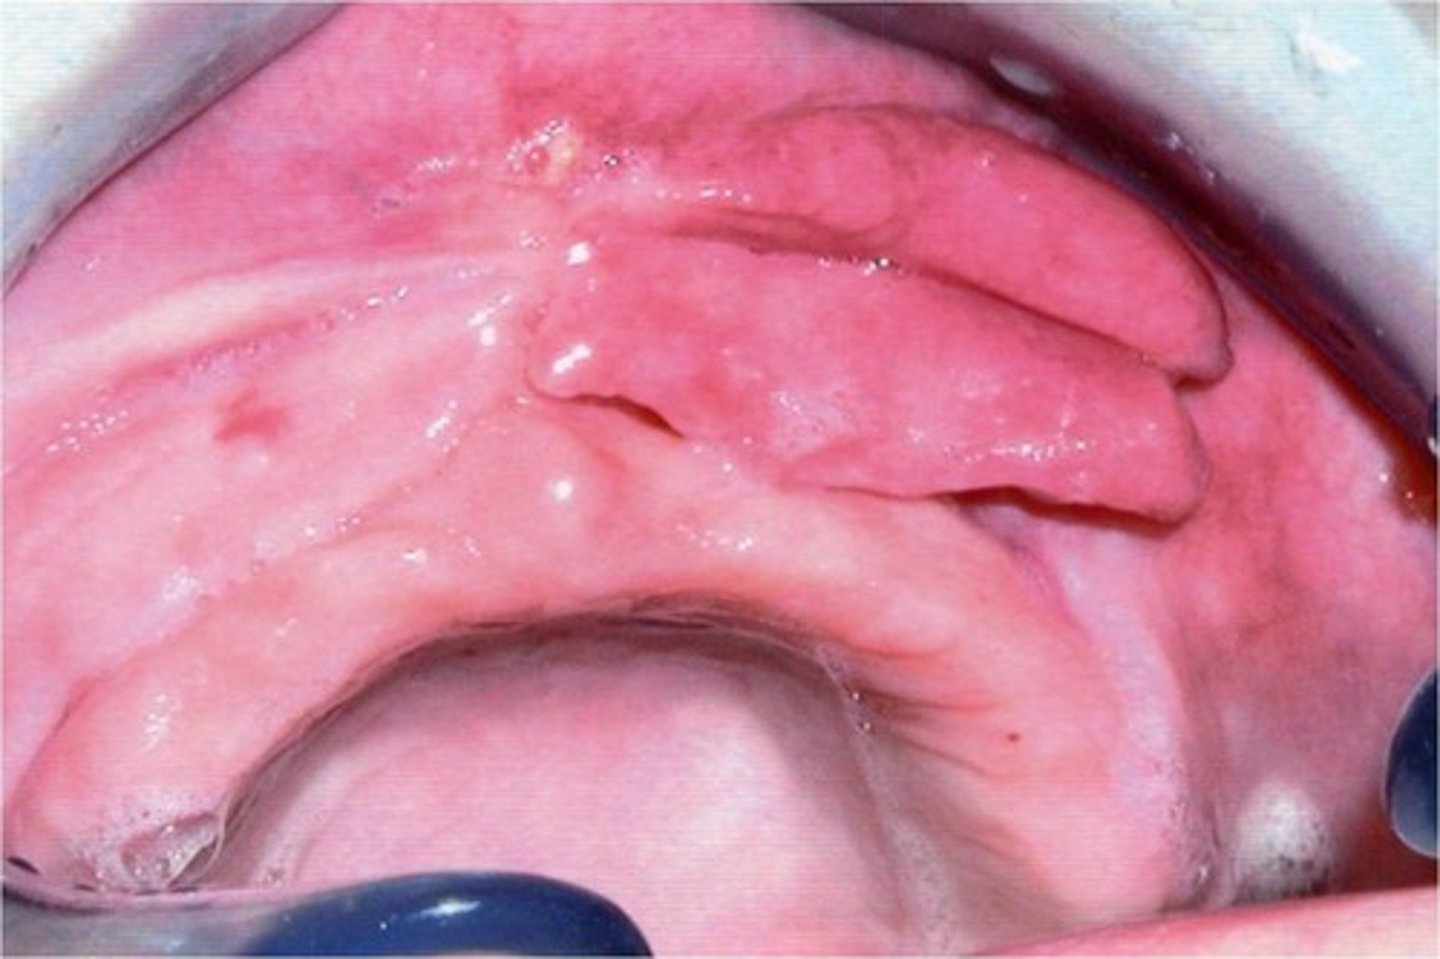

Question stem describes an epulis in a denture patient., photo included How would you treat?

- apply tissue conditioner

- leave alone

- prescribe antibiotics

- excision

excision